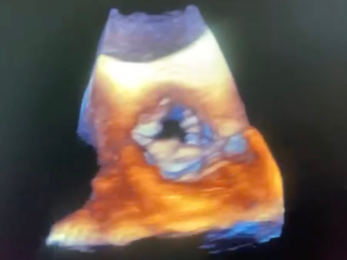

心脏彩超

• 主动脉峰值流速470cm/s,峰值压差88mmHg